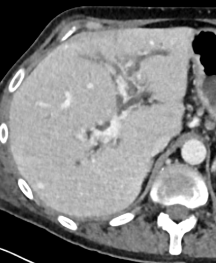

Module 1: Liver and biliary tract

Module coordinators : Prof. Christophe Aubé and Prof. Anita Paisant

- How to use hepatospecific contrast agents – advanced level

- Role of spectral CT in hepatobiliary diseases